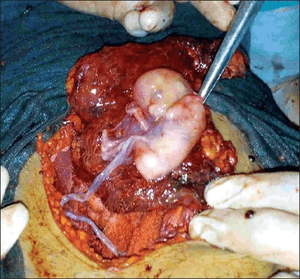

Abdominal pregnancy being delivered | |

An abdominal pregnancy can be regarded as a form of an ectopic pregnancy where the embryo or fetus is growing and developing outside the womb in the abdomen, but not in the Fallopian tube, ovary or broad ligament.[1][2][3]

It is generally recommended to perform a laparotomy when the diagnosis of an abdominal pregnancy is made.[12] However, if the baby is alive and medical support systems are in place, careful watching could be considered to bring the baby to viability.[12] Women with an abdominal pregnancy will not go into labor. Delivery in a case of an advanced abdominal pregnancy will have to be via laparotomy. The survival of the baby is reduced and high perinatal mortality rates between 40-95% have been reported.[33]